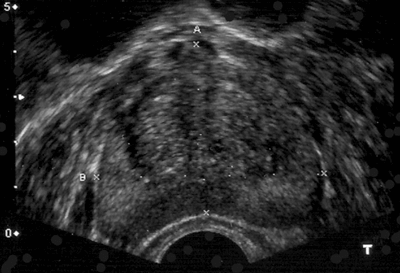

Figure 2: Transrectal ultrasound pre and post GreenLight vaporisation.